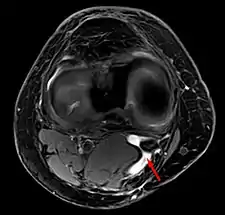

Un quiste de Baker en el espacio poplíteo

quiste de Baker en MRI axial con comunicación entre el músculo semimenbranoso y el the músculo gastrocnemius.